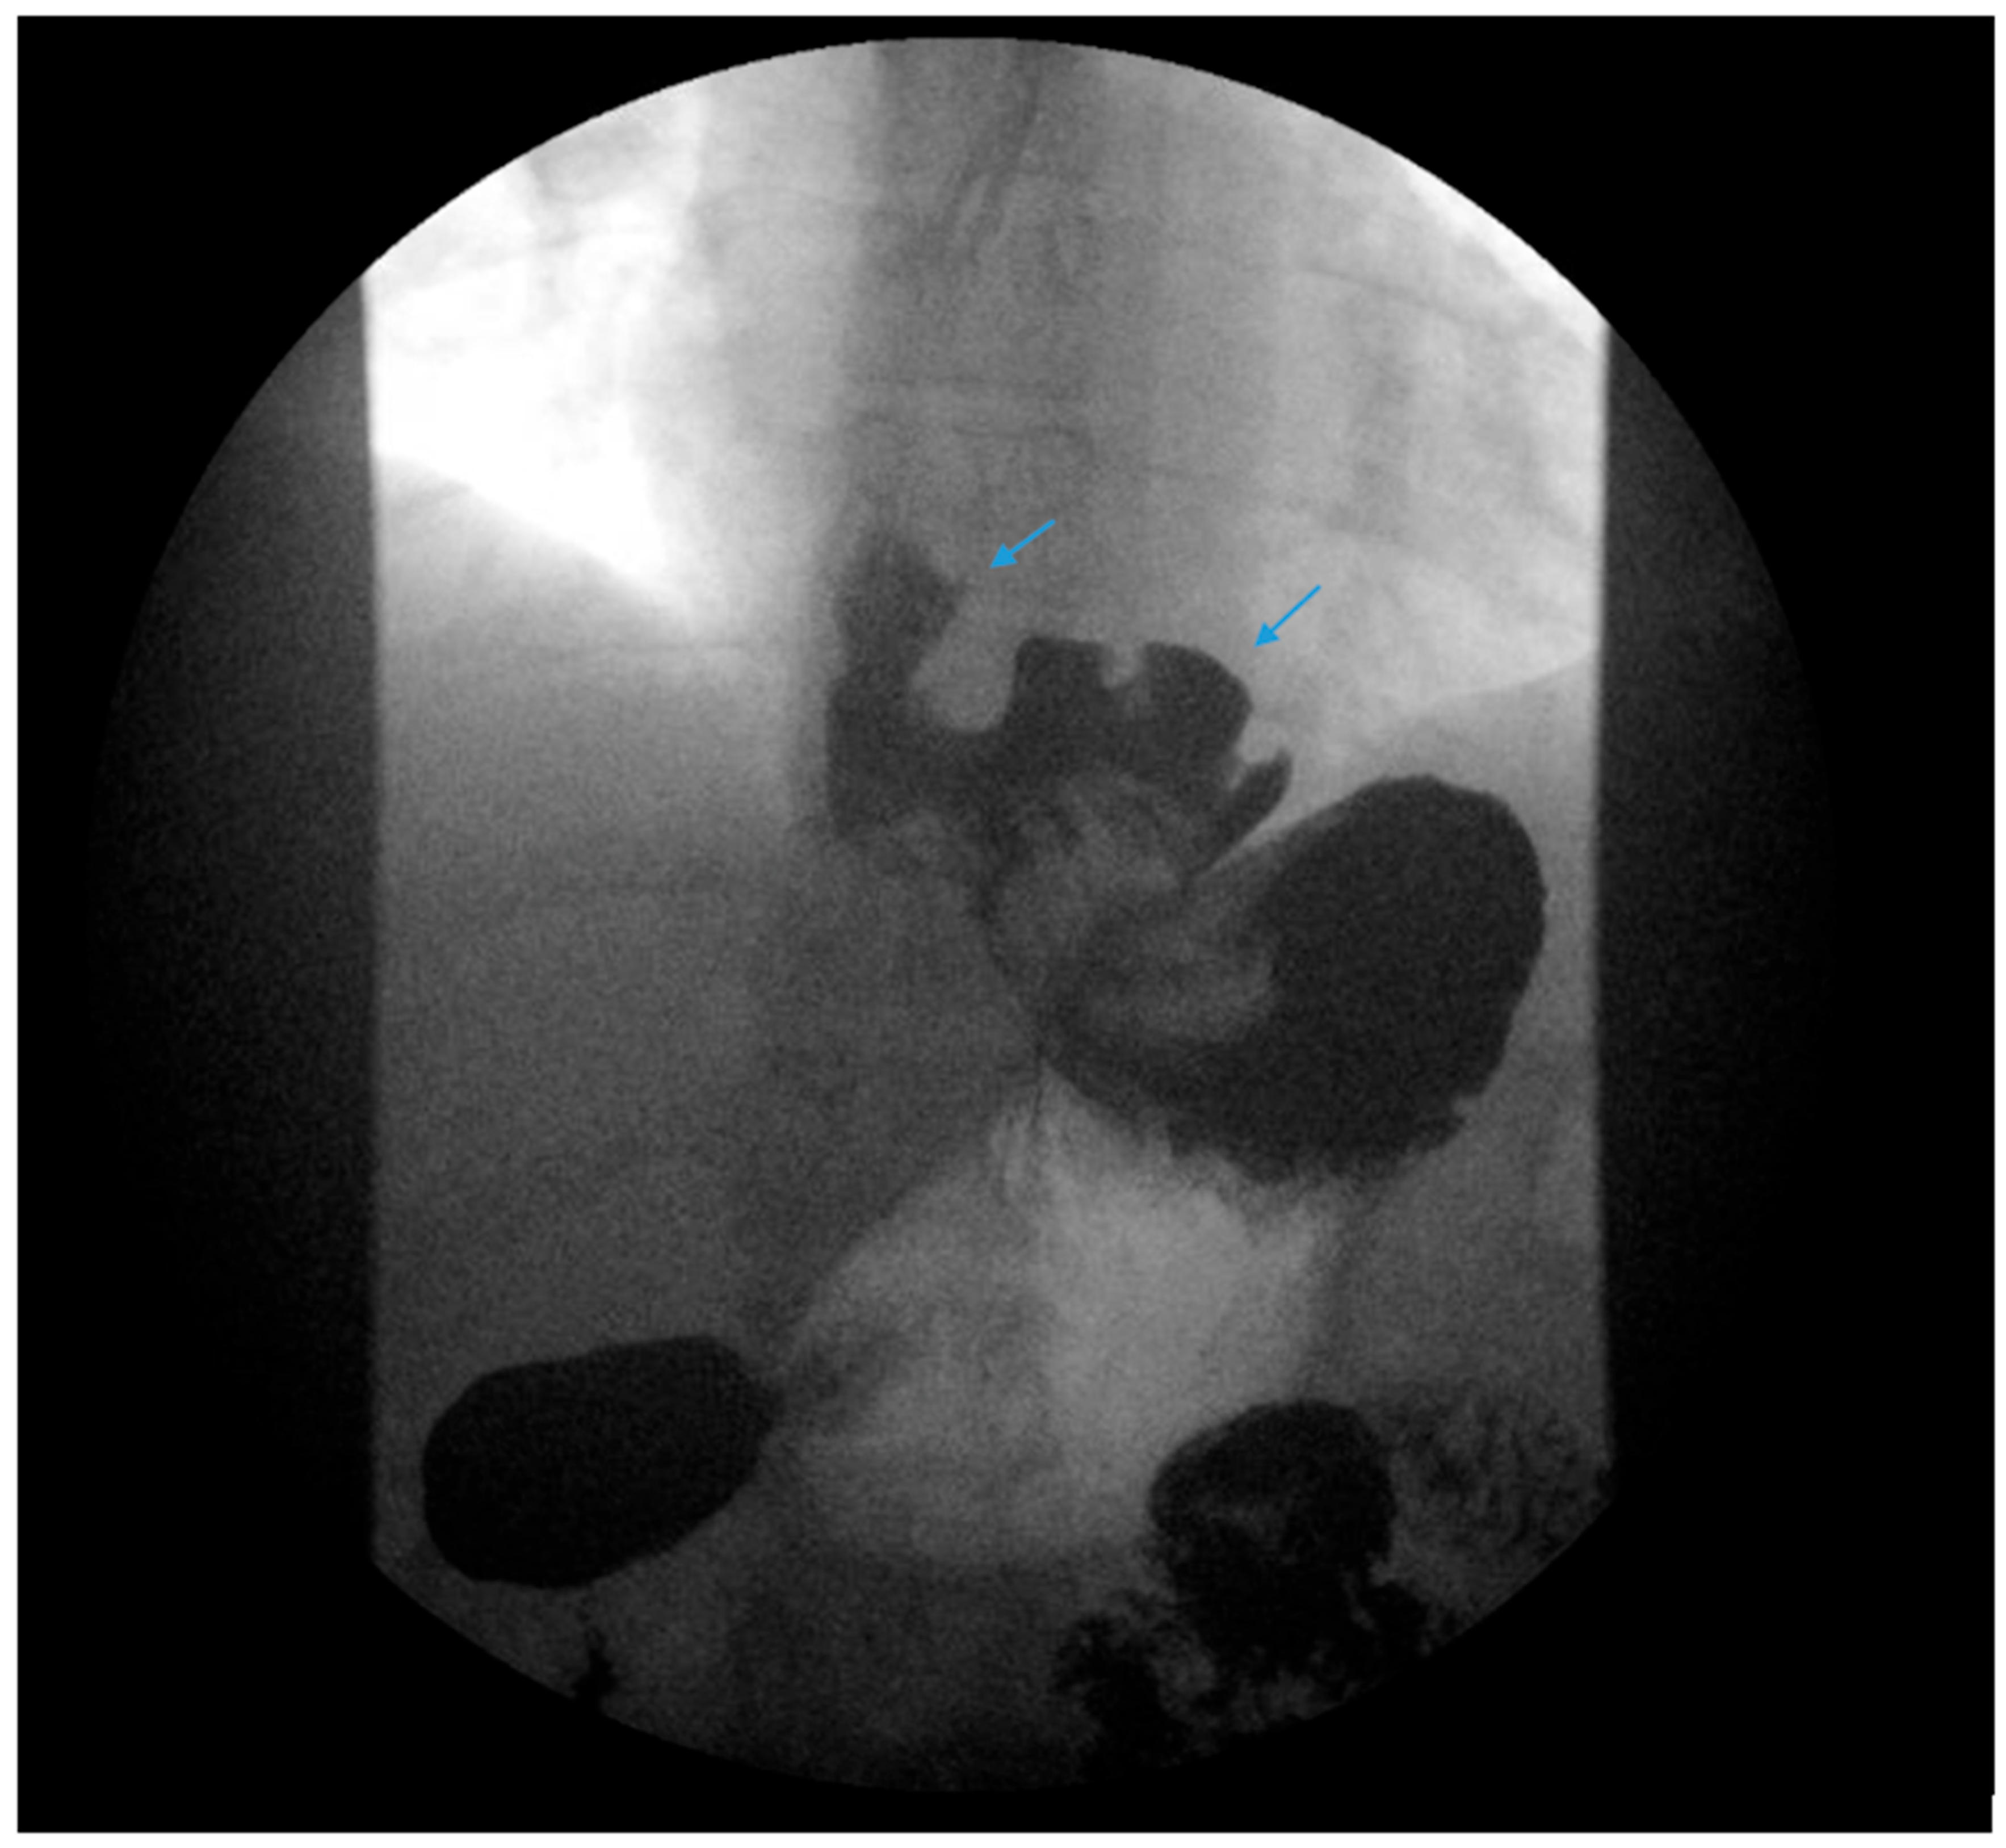

Figure 3.

An upper gastrointestinal series reveals contrast filling of sleeve with reflux of a column of contrast into the distal esophagus (blue arrow) in a patient following sleeve gastrectomy.

The authors recommend obtaining an esophagram, EGD, manometry and pH testing in selected patients presenting with GERD following SG for a further anatomic and physiologic evaluation of symptoms. Post-SG complications should be promptly identified and corrected. Stenosis, angulation and kinking of the gastric sleeve are associated with increased intragastric pressure and reflux (Figure 3) [38]. Ulcers and gastric sleeve leaks should be addressed appropriately.